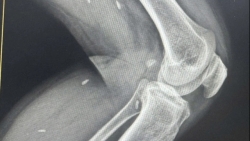

Bệnh nhân 14 tuổi, trú tại xã Lao Bảo, tỉnh Quảng Trị được đưa vào Khoa Hồi sức Cấp cứu (Bệnh viện Đa khoa tỉnh Quảng Trị) trong tình trạng nguy kịch sau tai nạn giao thông nghiêm trọng.